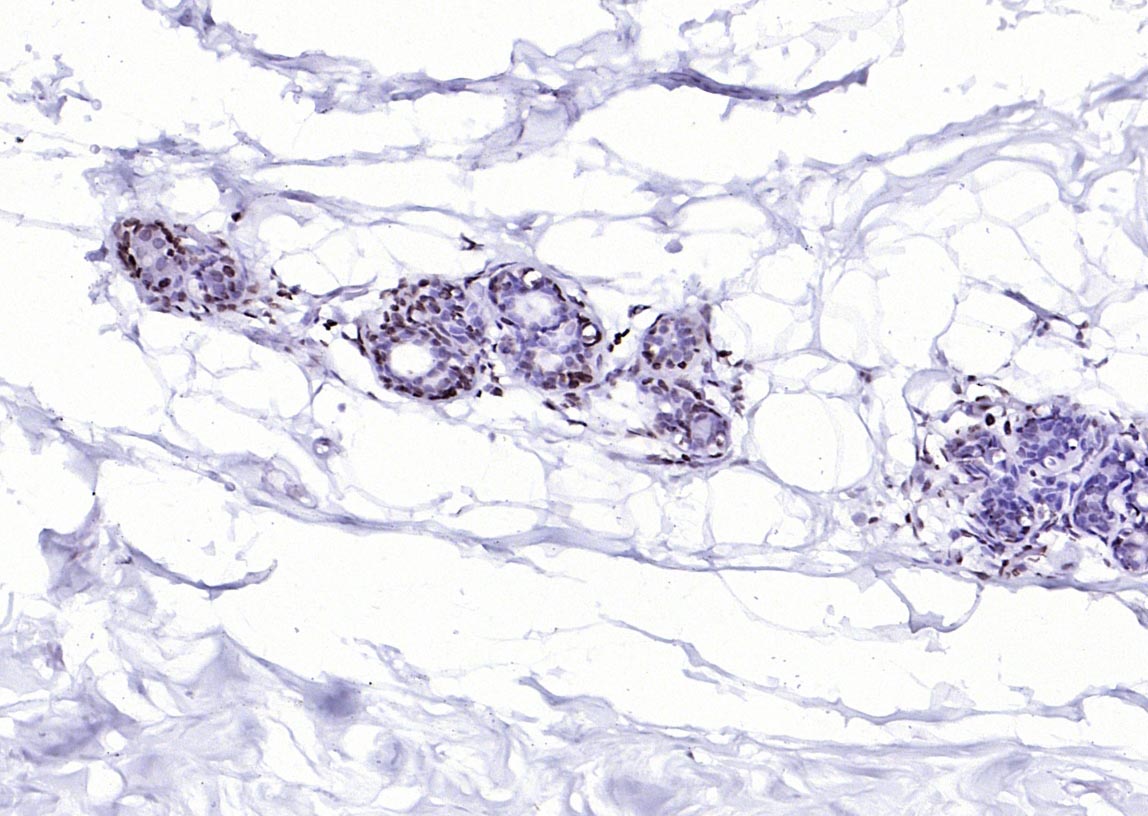

Paraformaldehyde-fixed, paraffin embedded (human breast); Antigen retrieval by boiling in sodium citrate buffer (pH6.0) for 15min; Block endogenous peroxidase by 3% hydrogen peroxide for 20 minutes; Blocking buffer (normal goat serum) at 37°C for 30min; Antibody incubation with (MYB) Polyclonal Antibody, Unconjugated (bs-5978R) at 1:200 overnight at 4°C, followed by operating according to SP Kit(Rabbit) (sp-0023) instructionsand DAB staining.